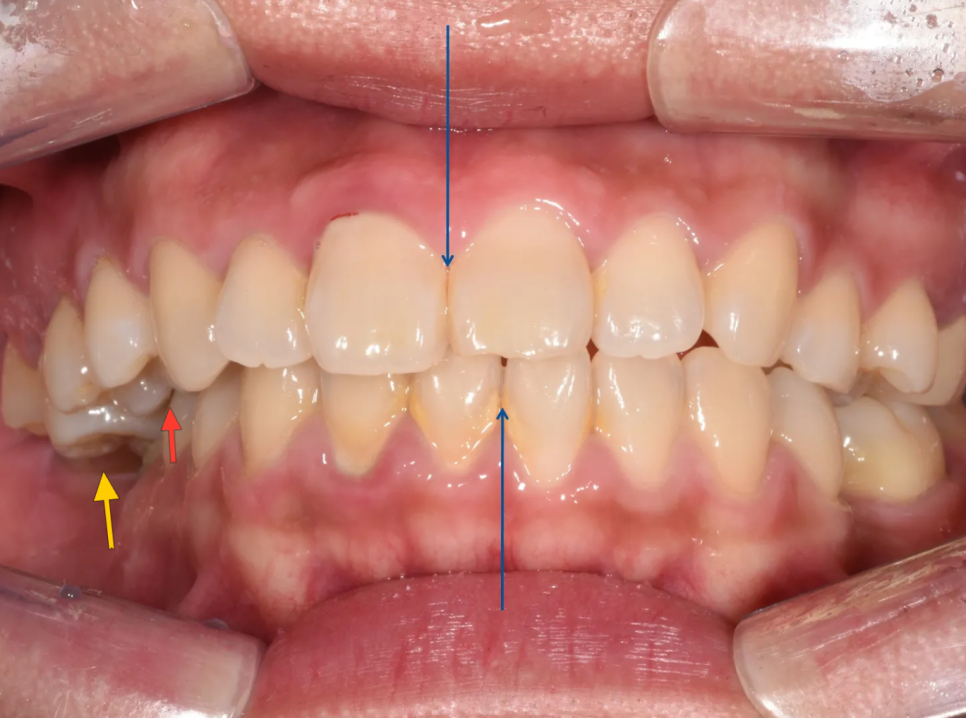

그런데 검진을 시작하자마자, 돌출입 외에도 여러 가지 문제들이 눈에 들어왔습니다. 오른쪽이 아예 물리지 않는 교합 불량, 어금니가 비정상적으로 내려온 상태(정출), 위아래 앞니가 너무 깊게 물리는 과개교합, 심한 충치, 그리고 이미 빠져 있는 치아까지. 단순 돌출입 교정이 아닌, 종합적인 교정 치료가 반드시 필요한 케이스였습니다.

위 어금니가 내려와있어서(노랑), 오른쪽은 이가 안 물리고 있고(빨강), 당연히 앞니의 중심선도 안맞습니다(파랑).